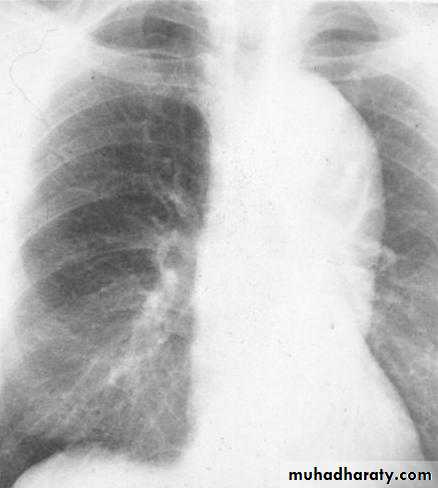

Pericardial effusion

occur when fluid collects in the pericardial space (a normal pericardial sac contains approximately 30-50 ml of fluid).radiographic features

Plain radiograph

a very small pericardial effusion can be occult on plain film, greater than 200 ml required to be visible radiographicly.

there can be globular enlargement of the cardiac shadow giving a water bottle configuration; known as Globe shape heart or pumpkin shape heart .